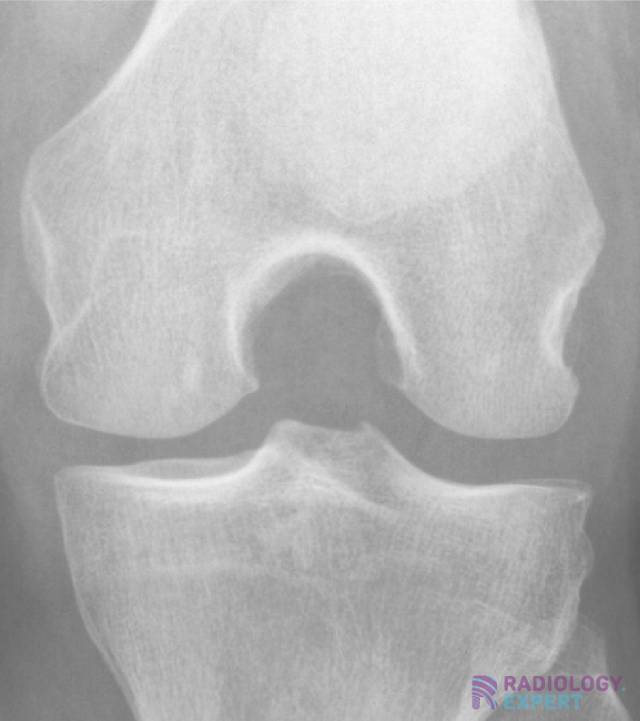

From www.radiology.expert

XKnee Best View For Knee X Ray Horizontal ray (lateromedial) = supine + knee extended. the rosenberg view of the knees is a specialized projection often used to detect early signs of osteoarthritis. the most common and standard for knee radiographs is the ap view or anteroposterior view. 45 degree pa flexion view (rosenberg view) best for early tibiofemoral arthritis, posterior wear The results. Best View For Knee X Ray.